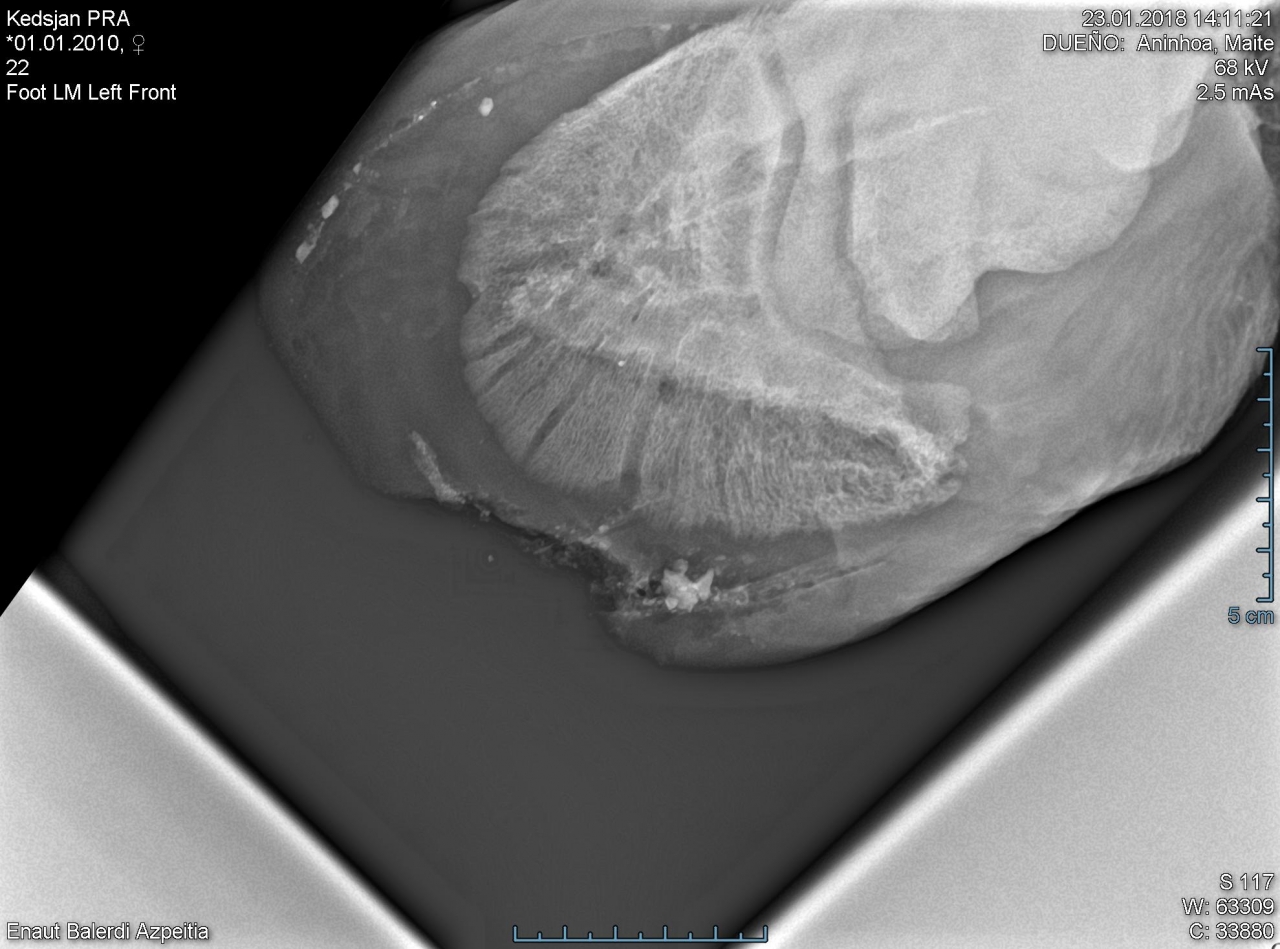

| Dire merci |

La radio de kesdjan... Il a fallu aller gratter sec, c était un pari mais le maréchal se le sentait, ça l à soulagé en svt |